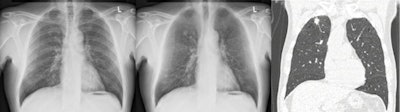

Bone suppression computer-aided detection (CAD) software can provide a significant boost for diagnosis of pulmonary nodules, especially those of moderate and subtle conspicuity, Dutch researchers have reported.

In a study conducted at Radboud University Nijmegen Medical Center, posteroanterior (PA) and lateral digital chest radiographs of 111 patients (average age 65) with a CT-proven solitary nodule (median diameter 15 mm), and 189 controls (average age 63) were read by five radiologists and three trainees. The total number of missed lesions for the eight readers went down from 255 with chest x-rays (CXR) only to 189 with CXR and bone-suppressed images (BSI).

"Obscuration of lung cancer by overlying bone structures represents a major contributor to misdiagnosis," they pointed out. "A new software product has been developed to suppress ribs and clavicles in the original image without requiring special hardware or increase of patient dose caused by double exposures."

Bone suppressed images were generated by ClearRead Bone Suppression 2.4 (Riverain Technologies). This software uses advanced image processing to construct a bone suppressed PA chest image, and it can produce an image that has the same characteristics as the original image with respect to gradation, detail contrast, and size. It has U.S. Food and Drug Administration (FDA) approval.

They classified the conspicuity of nodules as obvious (n = 32), moderate (n = 32), subtle (n = 29), and very subtle (n = 18). Observers read the PA and lateral chest radiographs with and without an additional PA BSI within one reading session.

Receiver operating characteristic (ROC) analysis showed improved detection with use of BSI compared with CXR alone (AUC = 0.883 versus 0.855; p = 0.004). Performance also increased at high specificities exceeding 80% (pAUC = 0.136 versus 0.124; p = 0.0007). Operating at a specificity of 90%, sensitivity increased with BSI from 66% to 71% (p = 0.0004). Increase of detection performance was highest for nodules with moderate and subtle conspicuity (p = 0.02; p = 0.03).